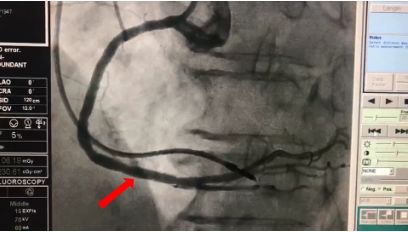

经过积极的前期处理及准备,患者存在的多种基础疾病相对稳定,心功能明显改善后,2018年6月21日在介入中心为患者行冠脉造影术,造影显示患者原左冠状动脉回旋支内植入支架通畅,而右冠状动脉内支架出现再狭窄达80%,结果与李主任的推断一致。支架内再狭窄的处理,可以选择的治疗手段有切割球囊、药物洗脱球囊、药物涂层支架等,切割球囊理论上可以将纵性斑块切开和扩张,因此可以获得较大的管腔,减少对血管的损伤,降低再狭窄发生率,还可以避免介入物的植入,符合目前最新的介入无植入的理念。

▲ 造影显示右冠状动脉

支架内再狭窄